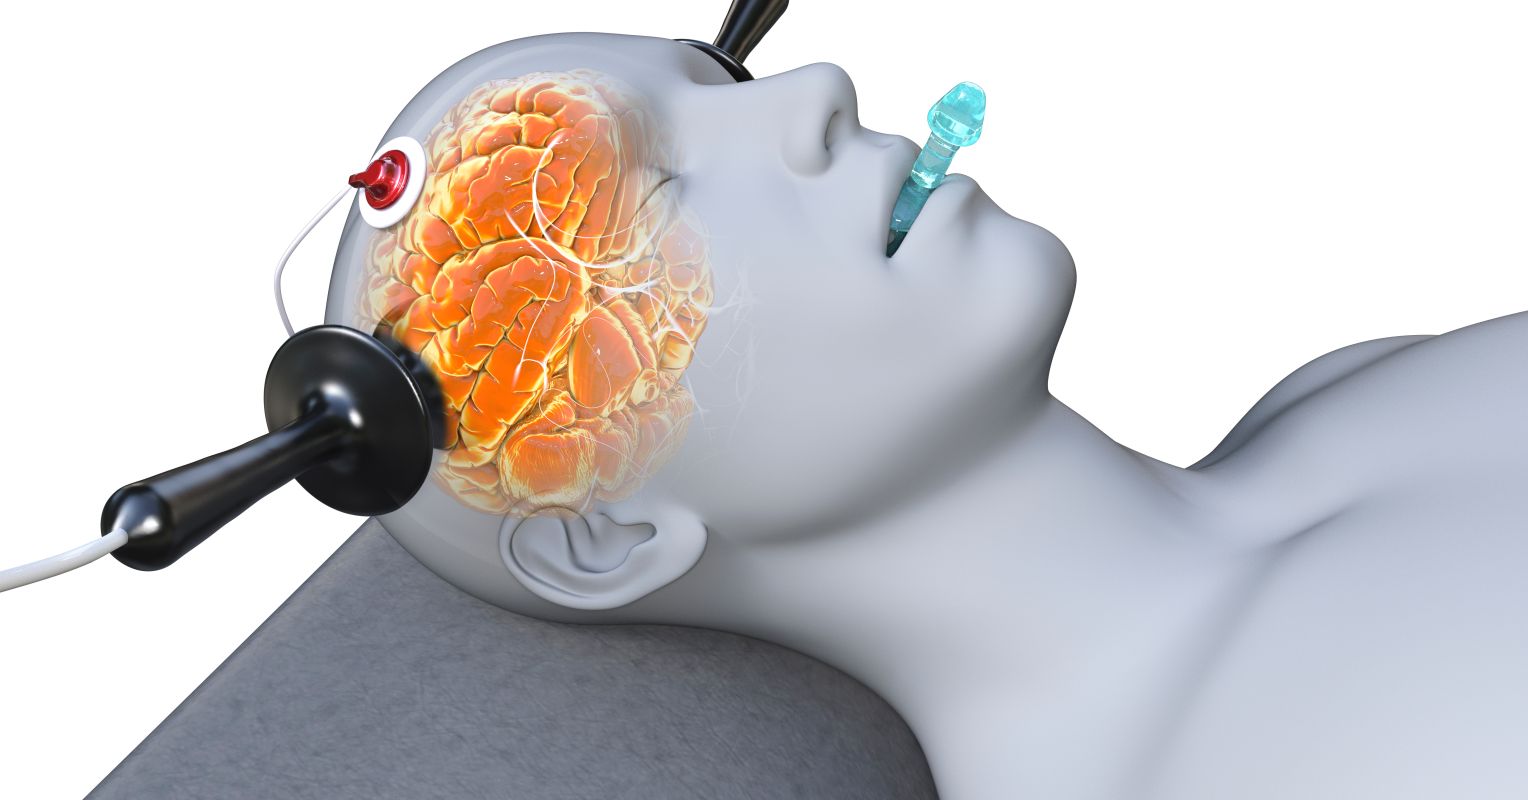

How Electroshock Remedy Adjusted My Lifestyle

[ad_1] In 1994, I experienced 1 of the worst depressive episodes I have ever endured. There was no query in my mind that demise was the only achievable solution for my ache. But my medical practitioners thought otherwise, and to humor them—I’m nothing at all if not a good patient—I allow them talk me into […]